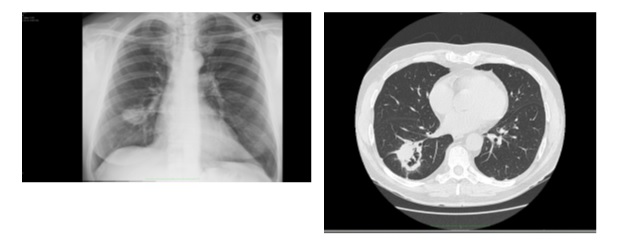

74-letni pacjent skierowany do poradni pneumonologicznej przez lekarza rodzinnego z rozpoznaniem nawracającego zapalenia płuc. Na podstawie wywiadu ustalono postępującą duszność wysiłkową, nikotynizm w wywiadzie 20-paczko lat. Choroby dodatkowe: nadciśnienie tętnicze dobrze kontrolowane. W ostatnim roku chory miał czterokrotnie podawane antybiotyki przez lekarza rodzinnego, lecz nigdy nie gorączkował. W badaniu fizykalnym stwierdzono obustronne metaliczne trzeszczenia nad dolnymi polami płucnym, w badaniach czynnościowych: FEV1/FVC 0,95; FEV1 35%N, FVC 28%N, TLC 32%N, DLCO 19,9 %N. Wykonano TK HRCT:

W oparciu o w/w: